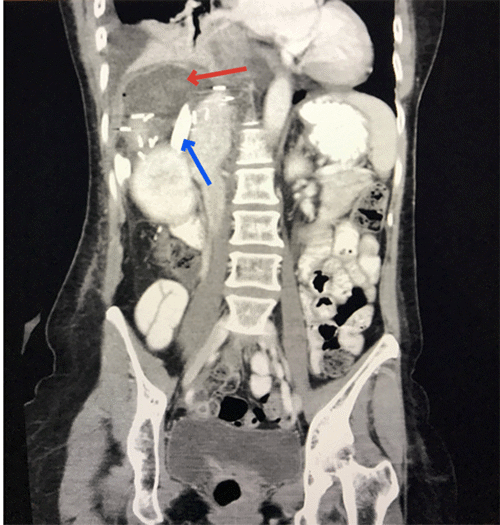

She was discharged to the ward on day 2. On day 3, the surgeon on the morning ward round noted 490 ml of intermittent bilious output from her drain as her synthetic liver function deteriorated. Endoscopic retrograde cholangiopancreatography was considered, and an expectant approach was adopted as the bile leak did not persist. Her liver function improved to baseline during her admission, but on day 12, in the setting of increasing fever and inflammatory markers, a CT of the abdomen and pelvis was performed (Figure 1). This demonstrated a 7.1 cm subcapsular collection with the drain tip positioned at its inferior aspect. She was placed on intravenous antibiotics and underwent an attempted percutaneous catheter (14 Fr Navarre) drainage of the collection (Figure 2). The procedure was completed successfully under adequate sedation. Unfortunately, however, the patient experienced severe pain refractory to analgesia during recovery.

Figure 2. Fluoroscopic Image Demonstrating Radiological Drainage. Published with Permission